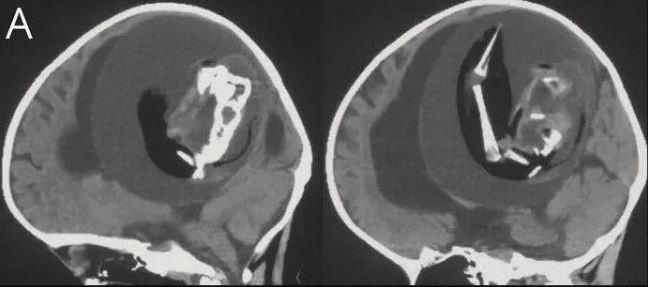

Bebeğin kafatasını çeşitli görüntüleme yöntemleriyle inceleyen araştırmacılar, beyninin sıkıştığını ve sıvı birikimi oluştuğunu tespit etti.

İleri incelemeler, bebeğin aslında anne karnındayken bir ikiz kardeşi olduğunu ama ikinci bebeğin yeterince gelişemeyerek kardeşinin kafatasının içine sıkıştığını ortaya çıkardı.

Sonuçta yeterince gelişemeyen bu embriyo diğeri tarafından içerilmişti. Böylece gelişmemiş olan bebek, diğerinin kafatasına sıkışmıştı.